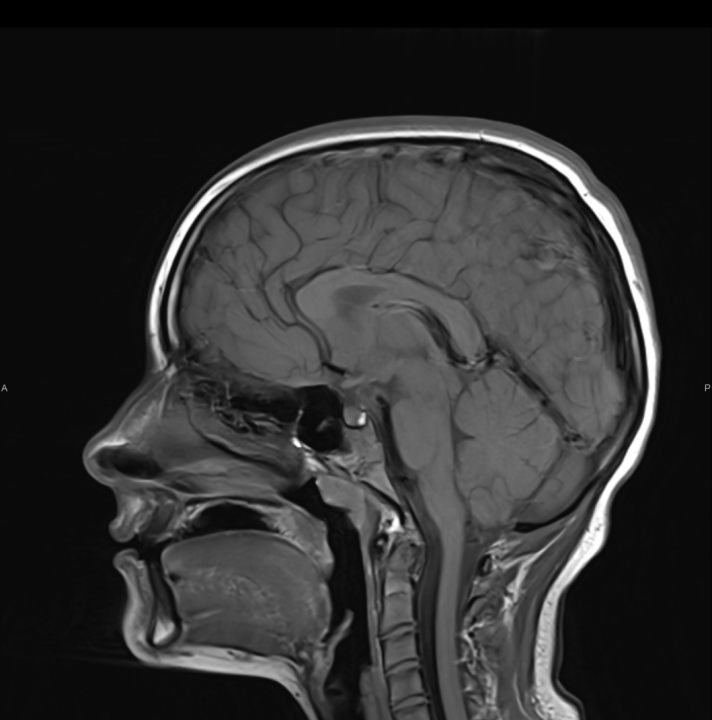

Tijekom Tjedna mozga Poliklinika Affidea Vita daje 20 posto popusta na magnetsku rezonancu!

Povodom obilježavanja Tjedna mozga od 11.